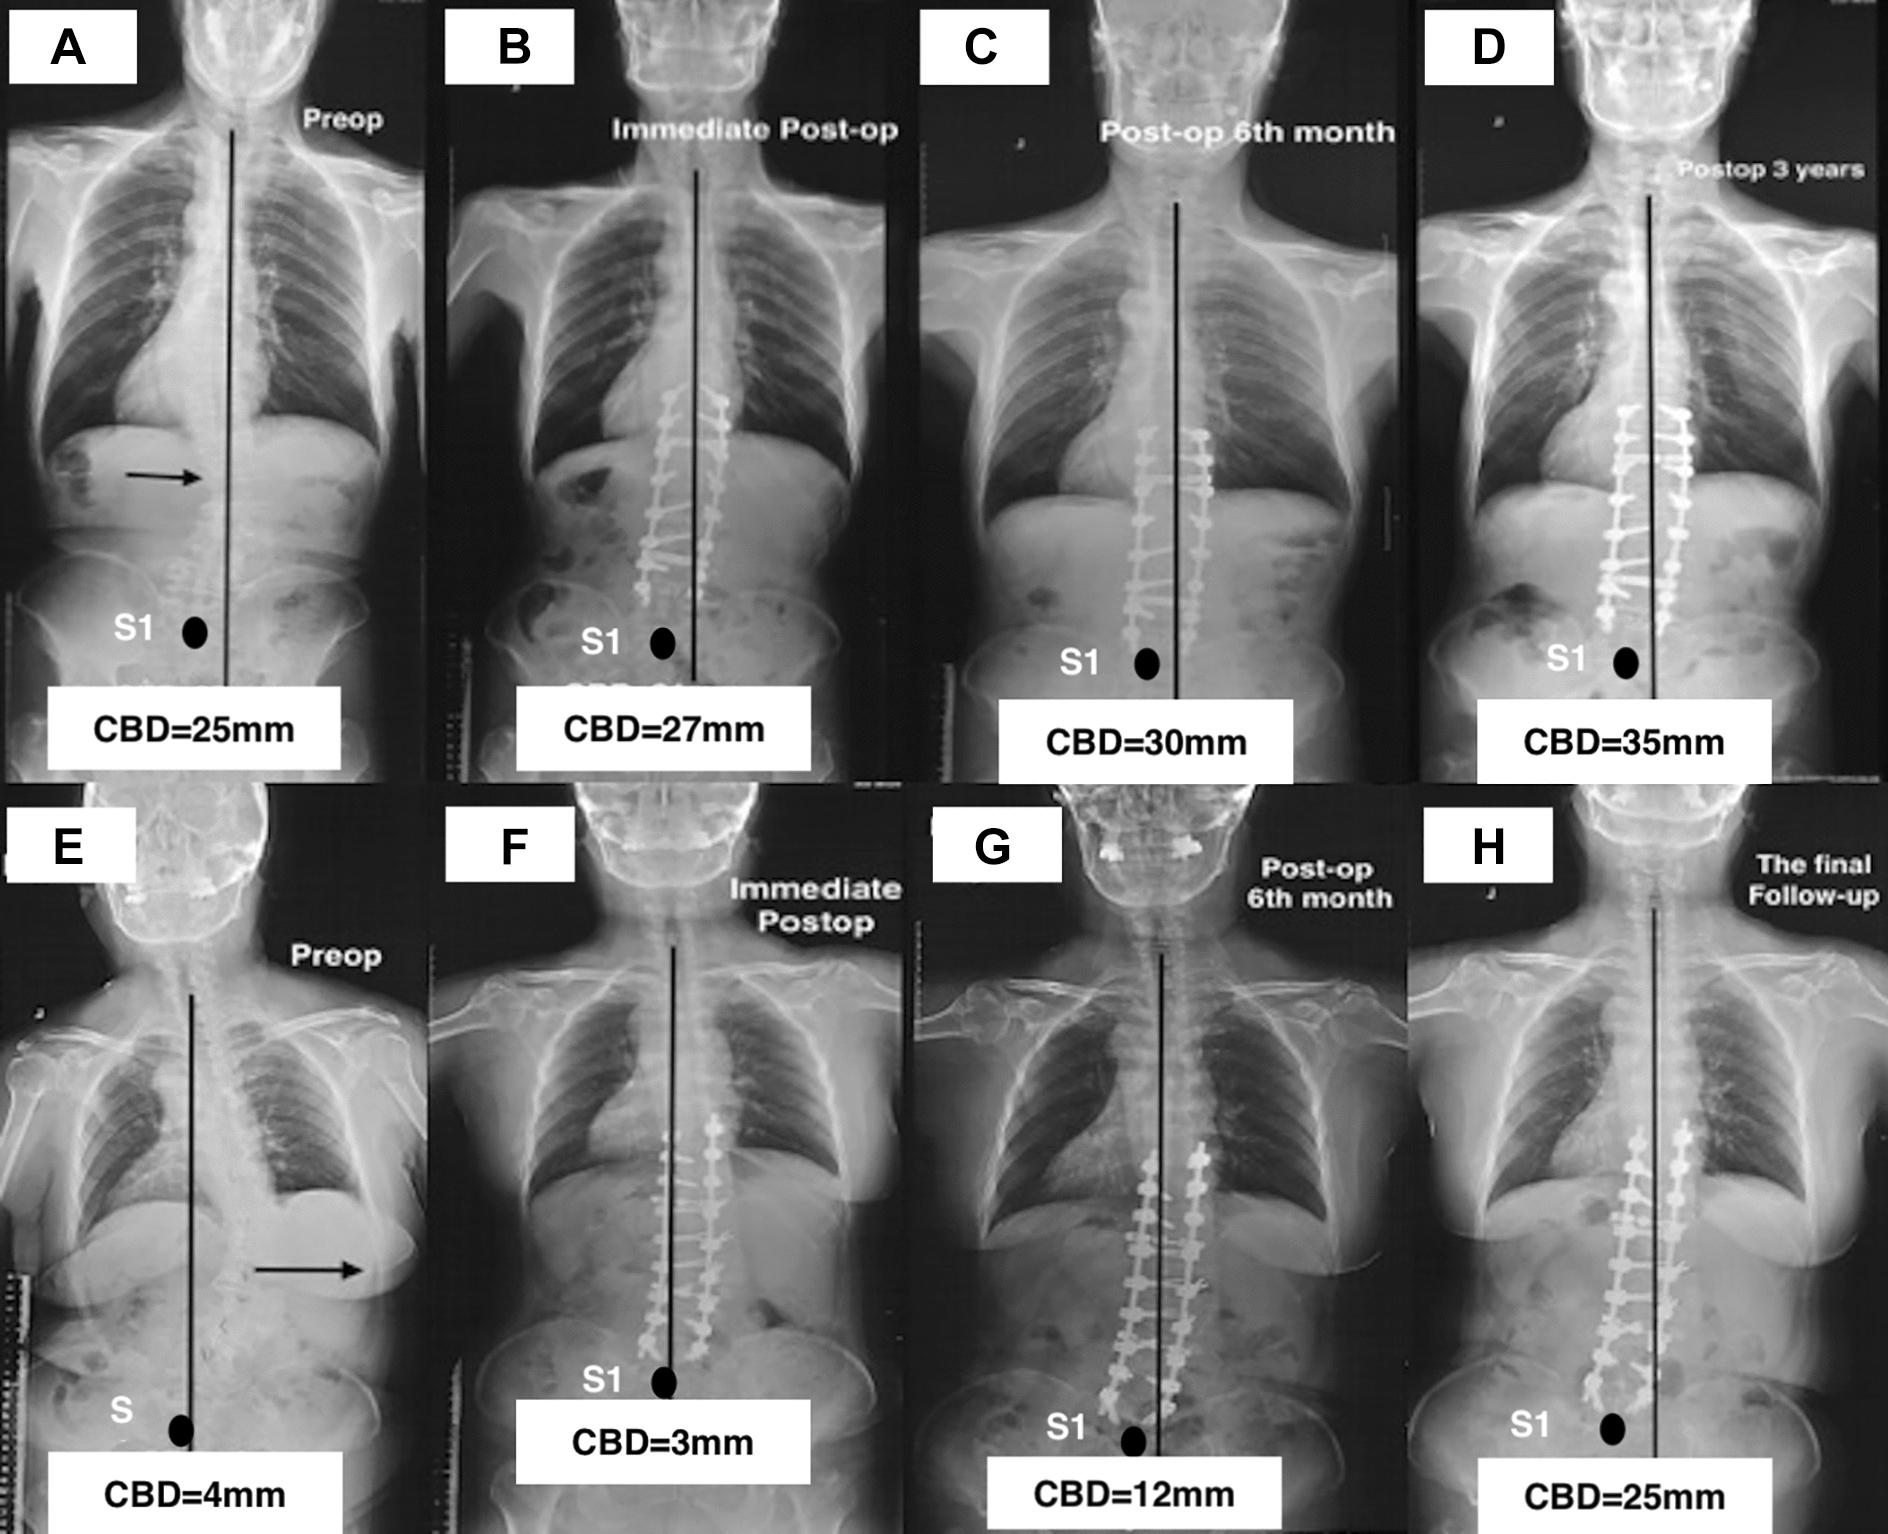

Two representative patients are shown in Figs. 4A–H and 5A–C.

More recently coronal malalignments (CM) in adult spinal deformity (ASD) have been reported, with new classification systems developed to further understand the effects of coronal deformities on pain, physical function and quality of life (QoL) [ref. 1, ref. 7, ref. 13]. The surgical procedure of long-fusion with instrumentations can restore the full-body alignments effectively in ASD [ref. 3, ref. 14, ref. 15]. Previous studies suggested that those individuals with the consistency coronal alignments (CA) preoperatively may be at the greatest risk for the immediate CM-happening postoperatively after scoliosis surgeries [ref. 1, ref. 7]. Therefore, we divided all subjects into the consistency group and the opposition group in this current study. Comparisons between the two groups showed that the CBD at the pre-operation had no differences; however, the CBD of the consistency group at the immediate post-operation and the final follow-up were much larger. Moreover, patients showing CM at the pre-, and post-operation were 35 (16 cases in the consistency group) and 45 (27 cases in the consistency group), respectively, and that increased up to 51 cases (35 cases in the consistency group) at the final follow-up. Comparing the incidence of CM preoperatively and that at the final follow-up, there were significant increases both in all cases and in the consistency group. Furthermore, after multivariate analyzing, the consistency CA was identified as the risk factor for CM-developing during follow-up. As shown in Fig. 4, a 61-year-old female ASD patient with the consistency CA had coronal balance both at the pre-operation and the immediate post-operation (Fig. 4A and B). During the follow-up, the CA gradually deteriorated, the CBD increasing up to 30 mm (Fig. 4C) at the 6th month after the surgery, and CM appeared at the final follow-up (CBD = 35 mm) (Fig. 4D). However, a 68-year-old female ASD patient underwent the similar thoracolumbar fusion surgery, maintained a benign CA throughout the follow-up (Fig. 4E–H). Accordingly, we insist that the consistency CA would be the risk factor for CM-developing in ASD underwent the surgical procedure of long-fusion with instrumentations.